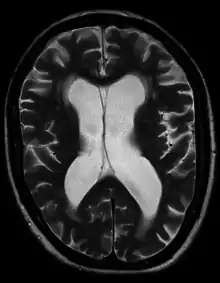

![]() | |

| Hydrocephalus as seen on a CT scan of the brain. The black areas in the middle of the brain (the lateral ventricles) are abnormally large and filled with fluid. | |